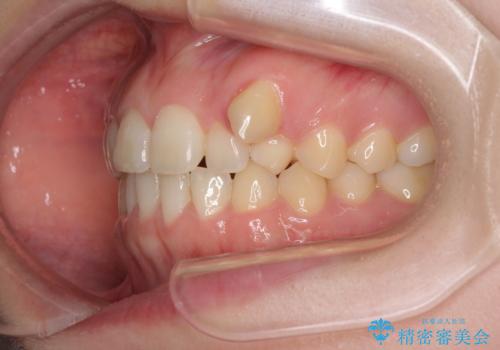

- 八重歯を気にして来院された患者様です。

八重歯のために乳歯が残存していたため、乳歯を抜去して八重歯となっている犬歯を歯列に収めることとしました。

八重歯の移動量が多くなるため、インビザラインと併用してワイヤー矯正を行い、八重歯を改善した後に、上下歯列をインビザラインで整えることとしました。